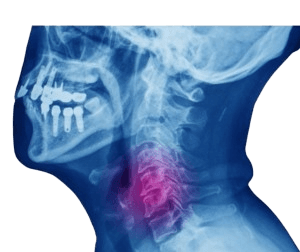

اعتلال النخاع الشوكي هو حالة تنتج عن ضغط على الحبل الشوكي أو إصابته. ونتيجة لذلك، قد يؤدي إلى الشعور بالألم، التنميل، وصعوبة في تحريك أجزاء معينة من الجسم. يحدث اعتلال النخاع الشوكي بسبب الإصابات الرضحية، التقدم في العمر، أو الانزلاق الغضروفي. في الواقع، قد تكون أعراض اعتلال النخاع الشوكي شديدة وقد تسوء إذا لم يتم علاجها أو تم تجاهلها.

الحبل الشوكي هو مجموعة من الأعصاب التي تنقل الإشارات بين الدماغ وبقية أجزاء الجسم. ويقع داخل القناة الفقرية المجوفة. كما تعمل عظام العمود الفقري كدرع واقٍ للحبل الشوكي. وقد تضعف الفقرات بسبب العديد من الأمراض والحالات.

يمكن أن يؤثر ضغط الحبل الشوكي على الأعصاب المسؤولة عن حركة الجسم ووظائفه، حيث يلعب كل جزء من الحبل الشوكي دورًا مختلفًا في وظائف الجسم.